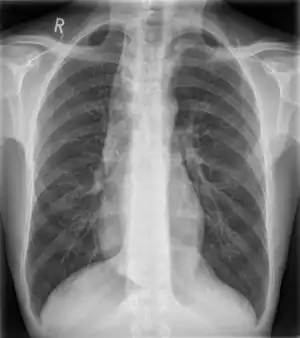

![]() | |

| Widened mediastinum in a patient with achalasia | |

Widened mediastinum/mediastinal widening is where the mediastinum has a width greater than 6 cm on an upright PA chest X-ray or 8 cm on supine AP chest film.[11]

A widened mediastinum can be indicative of several pathologies:[12][13]

- aortic aneurysm[14]

- aortic dissection[15]

- aortic unfolding

- aortic rupture

- hilar lymphadenopathy

- anthrax inhalation - a widened mediastinum was found in 7 of the first 10 victims infected by anthrax (Bacillus anthracis) in 2001.[16]

- esophageal rupture - presents usually with pneumomediastinum and pleural effusion. It is diagnosed with water-soluble swallowed contrast.

- mediastinal mass

- mediastinitis

- cardiac tamponade[17]

- pericardial effusion

- thoracic vertebrae fractures in trauma patients.